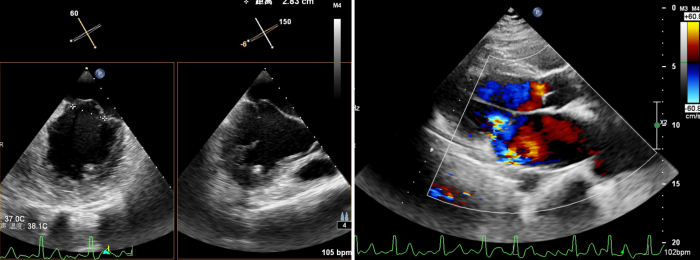

术后心脏彩超所示:二尖瓣无返流

术后,患者二尖瓣返流情况得到了明显改善,其他各项生理指标也均正常,术后第二天即可下床活动,呼吸困难和乏力症状显著缓解,心脏负荷明显减轻。术后心脏彩超结果显示,其左室射血分数上升到62%,生活质量获得极大提升。